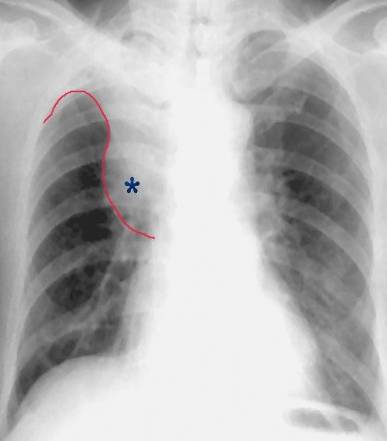

传统方法采用X线检测肿瘤癌症,可以看到肺癌的部位和大小,还能看到由于肿瘤阻塞支气管引起的肺气肿、肺不张、肺炎或胸腔积液等,是肺癌初步诊断的首选检查。

但是很多肺部疾病也表现为肺部的一个肿块阴影,所以需要进一步鉴别;此外,有些肺癌长在心脏后方的肺组织里,在胸片上,肿瘤影和心影重叠在一起,也很难判断。因此,很多患者,特别是高度疑诊的病例常常需要进一步检查。